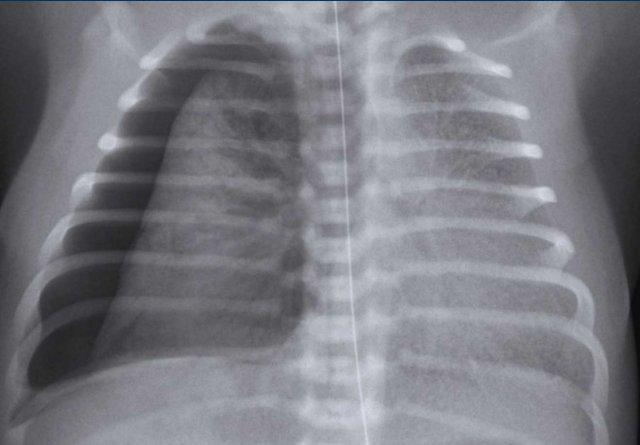

Trẻ sơ sinh 41 tuần tuổi thai. 24 giờ tuổi.

Suy hô hấp, không hỗ trợ thở máy

Image

- Marked

hyperinflation of both lungs - Increased

vascular markings and interstitial markings - Some interfissural fluid (arrow).

Spontaneous improvement within 48 hours.